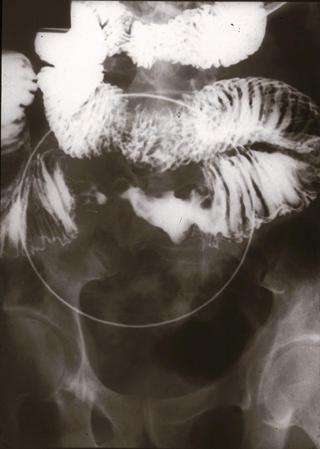

clasificación del pacienteTumor Maligno del Sistema Linfático/Linfoma Maligno

parte(separada por órganos)intestino delgado/yeyuno

método de exámenRayos X

grado de penetracións(a)

múltiples tumores(en un mismo órgano)presente(simultáneo)

múltiples tumores(en varios órganos)presente(simultáneo)